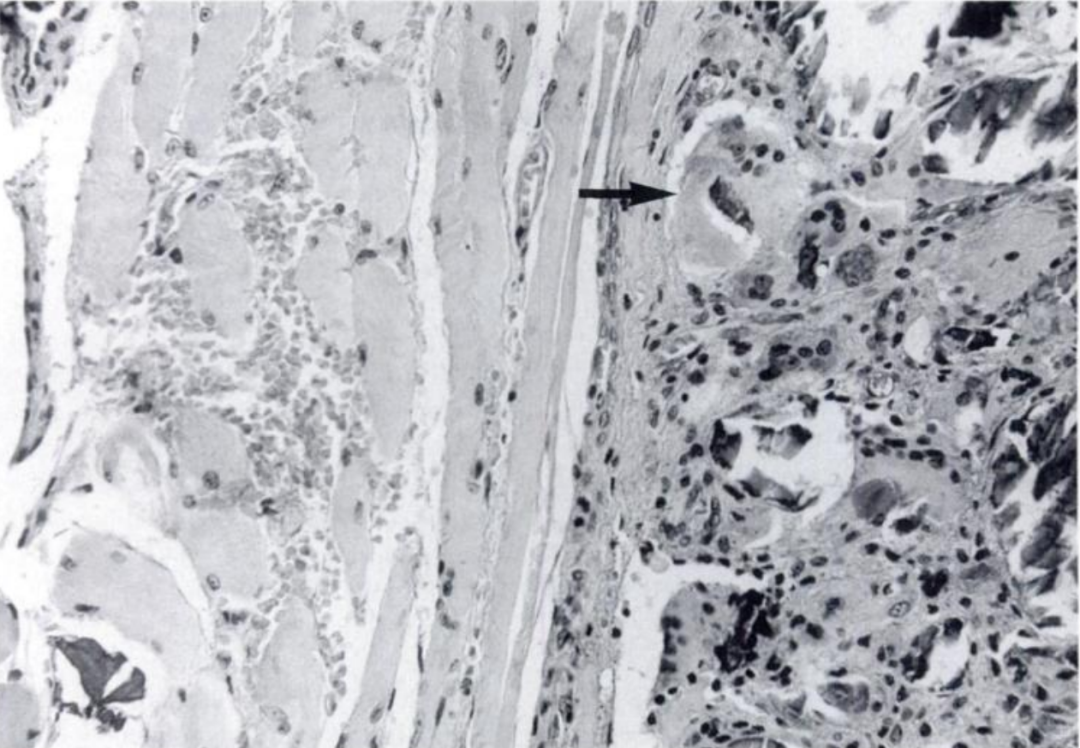

目前认为,颈长肌钙化性肌腱炎是由颈长肌肌腱内羟基磷灰石晶体沉积引起,并伴有无菌性炎症反应。

图:光镜可见典型的钙质肉芽肿病变,多核巨噬细胞吞噬钙质结晶(箭头)